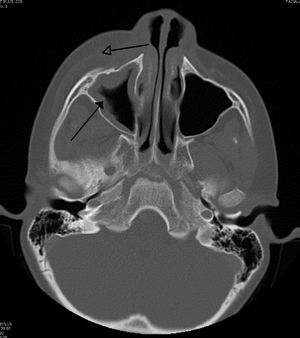

| التهاب الهلل حول الحجاج الناجم عن عدوى بالأسنان (تسبب أيضًا التهاب الجيوب الأنفية) | |

يجب التمييز بين التهاب الهلل حول الحجاج والتهاب الهلل المحجري ، وهو حالة طارئة ويتطلب مضادات حيوية عن طريق الوريد (IV). على عكس التهاب الهلل المحجري ، لا يعاني المرضى المصابون بالتهاب الهلل حول الحجاج من انتفاخ في العين ( جحوظ العين ) ، أو حركة محدودة للعين ( شلل في العين ) ، أو ألم في حركة العين ، أو فقدان الرؤية. في حالة وجود أي من هذه الأعراض ، يجب على المرء أن يفترض أن المريض يعاني من التهاب الهلل المحجري ويبدأ العلاج بالمضادات الحيوية الوريدية. يمكن إجراء الفحص بالأشعة المقطعية لتحديد امتداد العدوى.

تشمل الاختبارات تحاليل الدم (CBC) لاستبعاد السبب المعدي. قم أيضًا بإجراء فحص بالأشعة المقطعية والأشعة السينية للجمجمة الأمامية لعرض الجيوب الأنفية ومسح التصوير بالرنين المغناطيسي وأخيراً الموجات فوق الصوتية للأنسجة الرخوة في المنطقة الحجاجية